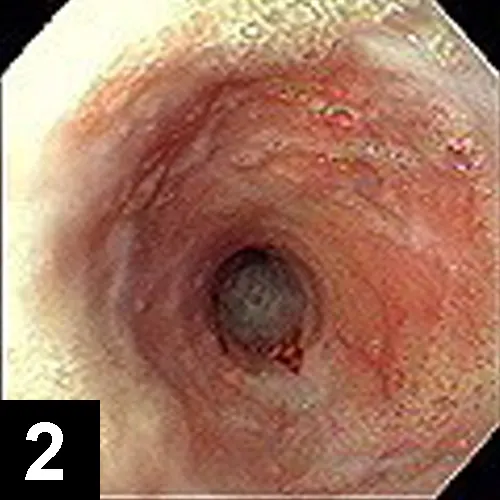

The most likely cause of this abnormality is an intramural esophageal stricture. Unlikely causes for esophageal narrowing include extrinsic extraesophageal compression from neoplasia or inflammation, vascular ring anomaly, presence of an esophageal foreign body, or esophageal neoplasia. Endoscopy was done to delineate the obstruction and to perform therapeutic esophageal dilatation. Figure 2 shows the esophageal narrowing at the thoracic inlet. Figure 3 shows the esophagus following a balloon dilatation procedure.

Figure 3. The esophageal stricture after dilatation to 16 mm diameter

Treatment Plan. Feed a liquid diet or attempt to dilate the stricture. Surgical resection is considered to be less successful. Several dilatation instruments have been described, but dilatation with a balloon seems to be the safest and most successful method. Balloons of increasing diameter are inserted into the lumen and then inflated under pressure to open the lumen to the desired diameter. In this case, the stricture was dilated to 16 mm in diameter over a course of three sessions at weekly intervals. Some authors recommend systemic or intralesional injections of steroids to reduce inflammation and stricture contraction. This cat was also treated with intralesional injections of triamcinolone in the stricture site using an endoscopic injection needle. It made an uneventful recovery and now consumes canned food without problems.